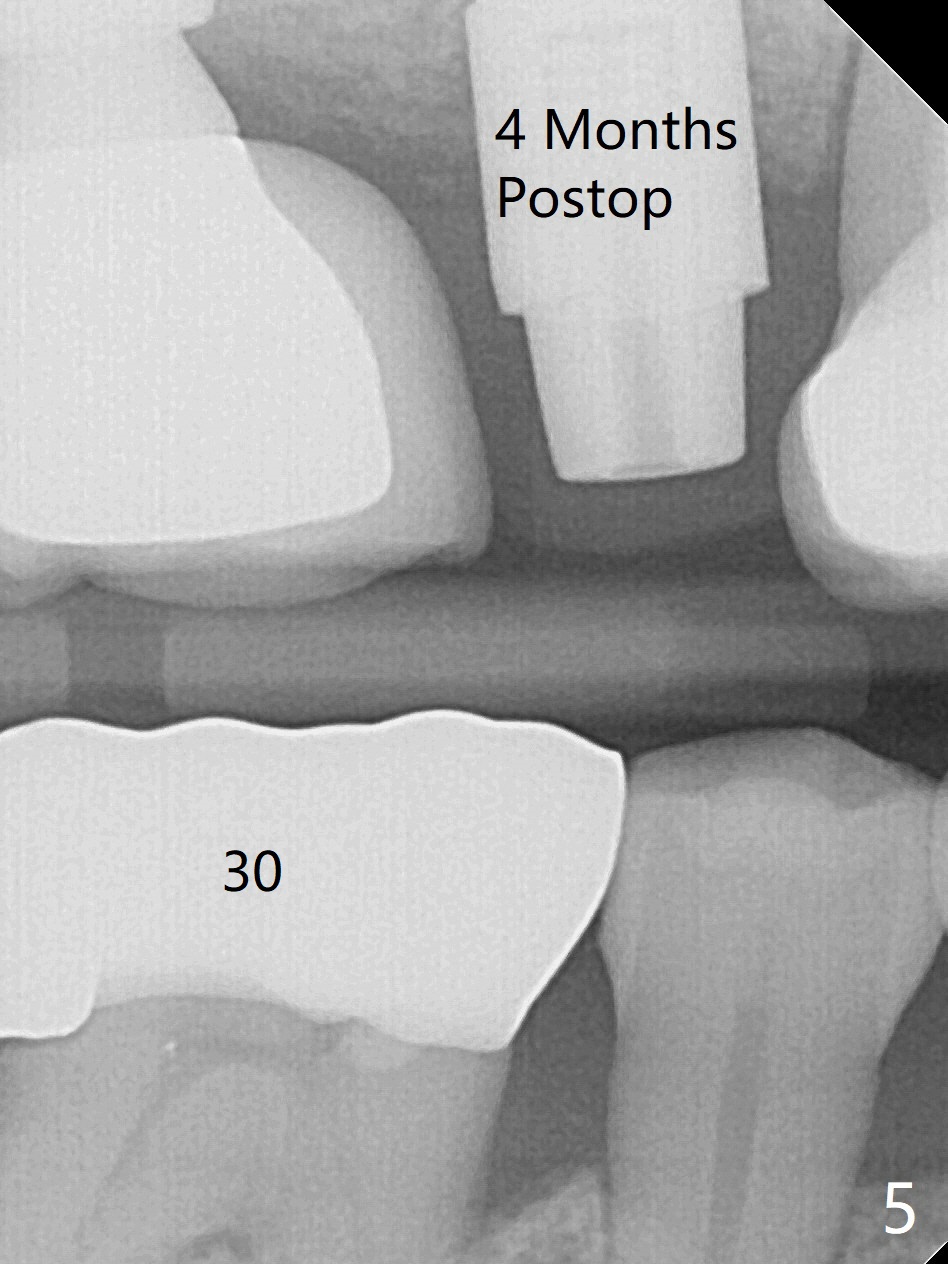

In spite of a fistula at #4, the buccal plate is present because of the exostosis (Fig.1 *). Since the socket is long and narrow, it is difficult to initiate osteotomy in the distal slope. Since the buccal plate is low, osteotomy is established as palatal as possible. The sinus floor is thin, but hard to elevate with Magic Sinus Lifter. Use of 3 mm Magic Expander leads to sinus floor break through and membrane perforation. After increase in the osteotomy with sequential expanders, a 5x20 mm tap is inserted with stability (Fig.2). Two pieces of PRF membrane are inserted for sinus membrane repair, followed by small amount of allograft (mixed with PRF, Fig.3 *) and a 4.5x17 mm dummy implant. A 5x17 mm tissue level implant is placed with >45 Ncm; with immediate placement of a 4x3 mm abutment (Fig.4), an immediate provisional is fabricated. There is no postop nasal hemorrhage. The immediate provisional has occlusal perforation 1.5 months postop. The tooth #13 has mobility due to its overuse and missing the teeth #14 and 18. Bitewing taken while redoing crown for #30 shows that the implant threads are subcrestal (Fig.5). There is no crestal bone resorption 6.5 months postop (Fig.6,7), while the periradicular radiolucency decreases (Fig.7).